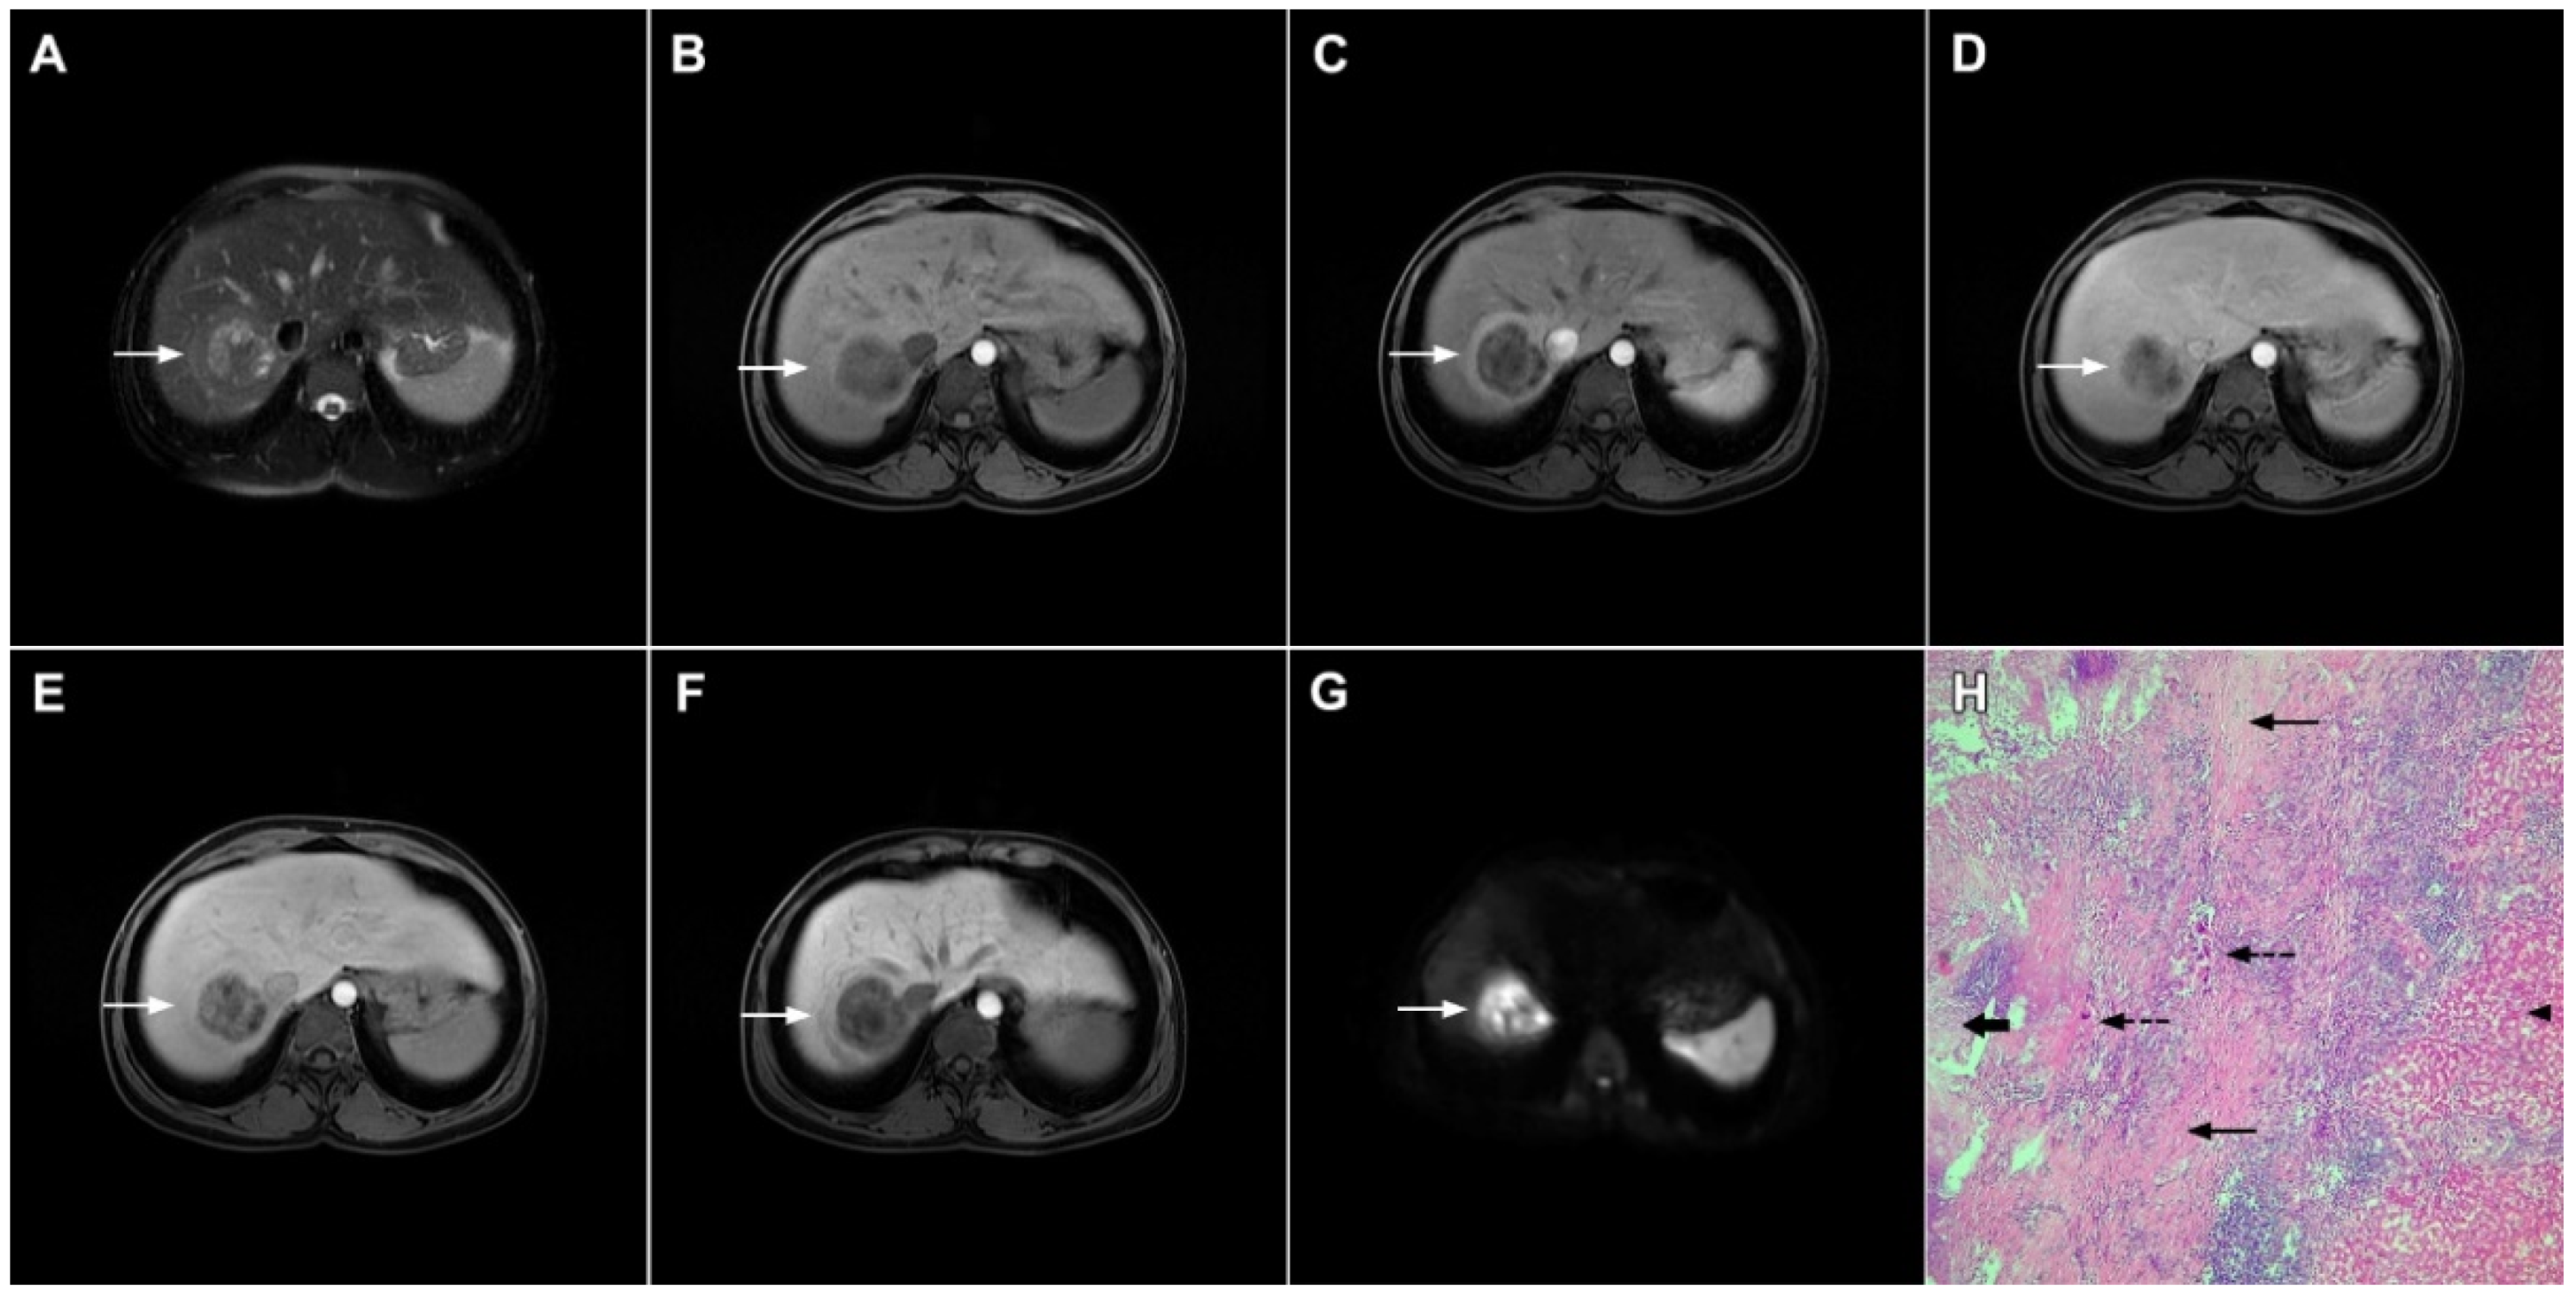

Figure 6.

Hypervascular mass-forming cholangiocarcinoma in a 63-year-old woman. The axial T2-weighted image (A) shows a moderately hyperintense tumor (arrow) located in liver segments VI and VII with a subtle medial capsular retraction. The lesion (arrow) is hypointense on the plain T1-weighted image (B), hypervascular in the arterial phase (C) with washout on the portal venous phase (D). The tumor (arrow) is hyperintense on DWI (E). Hematoxylin and eosin (H&E) staining (F) showed well-differentiated cholangiocarcinoma (arrow) surrounded by normal liver parenchyma (dashed arrow); original magnification ×40.